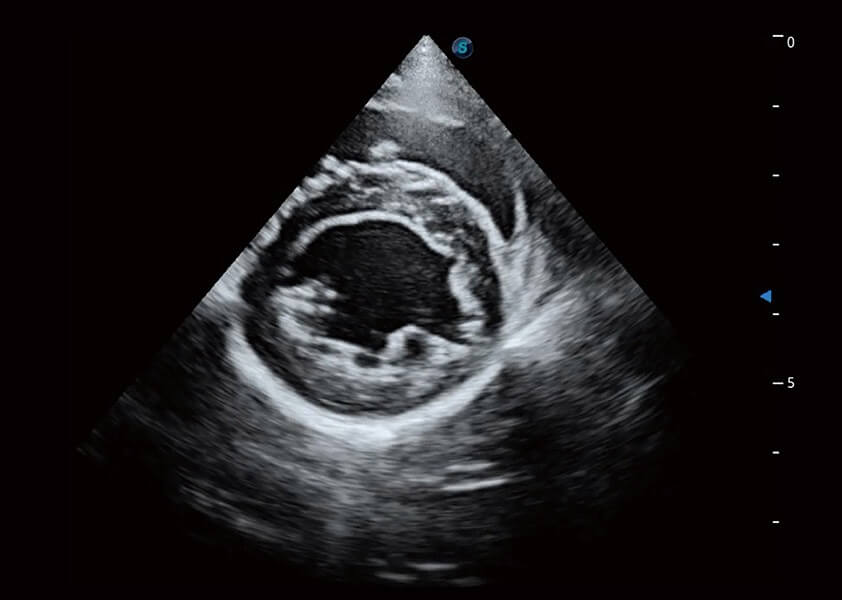

(犬)乳头肌短轴

(猫)二尖瓣M型

心脏解决方案

ProPet 60 配备了丰富的心脏探头群、先进的成像技术和专业的心脏测量工具,可帮助动物医生为不同体型和生理结构的动物提供心脏和心肌功能的全面评估。

• AMM 解剖M型

通过360度任意调节3条M型取样线,在同一心动周期上观察心脏不同位置的运动曲线,得到准确的心功能测量数据,有效评估心肌运动及左心室功能。